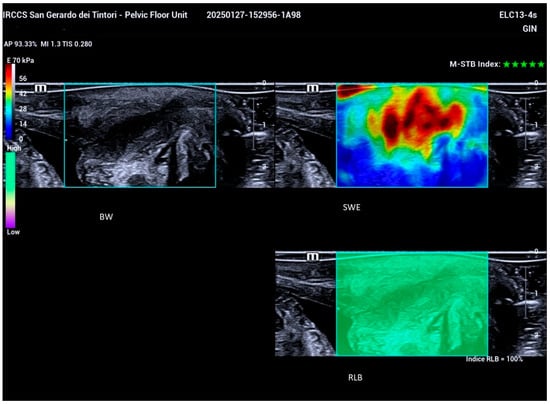

2.2. Ultrasound Examination